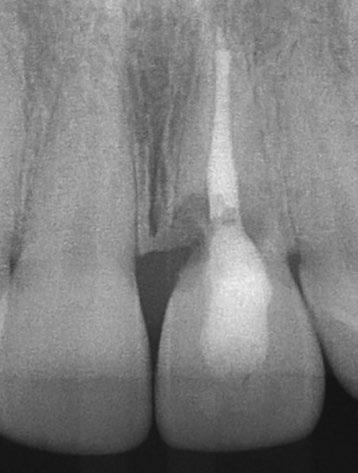

Su solicitud inicial es volver a blanquear el 21, que había sido previamente endodonciado y había recibido sucesivos tratamientos blanqueadores que habían recidivado. Refiere ligera molestia en la papila interincisiva. En la exploración radiográfica intraoral 1 2

11

se aprecia una extensa reabsorción radicular interna, con el consiguiente defecto óseo, que se confirma con un CBCT (Fig. 3, 4, 5). Se informa a la paciente del riesgo de fractura espontanea. Esta solicita solucionar el problema antes de que avance más.